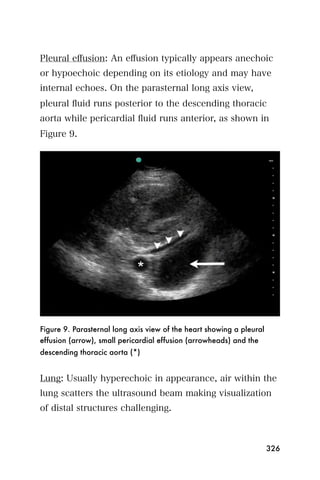

Abdominal circumference

For the Abdominal Circumference (AC), ensure that the

measurement of the fetal abdomen is in an axial plane,

121

and that the following landmarks can be identified: